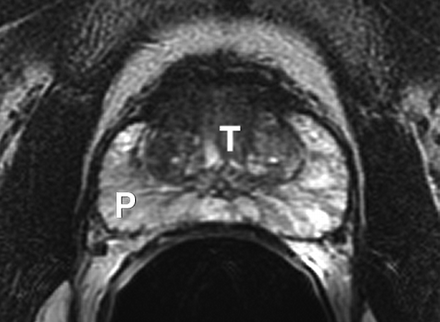

Most prostate cancers arise in the peripheral zone (PZ) [5], a region that may be compressed by the expanding transition zone (TZ) when there is significant BPH.

To improve PZ sampling it has been proposed that needle placement for systematic biopsies be directed more laterally [6], so that the biopsy tract traverses more of the PZ and encompasses the lateral PZ.

Sextant biopsies were taken routinely ≈ 1 cm apart in the parasaggital plane bilaterally, at the base, mid-gland and apical regions of the prostate, as described by Hodge et al. [1]. In addition, six further biopsies were obtained, two from the TZ and four from the lateral PZ, as depicted in Fig. 1. The TZ biopsies were taken at the level of the mid-gland where the TZ was most prominent. The lateral PZ biopsies were taken by positioning the probe just medial to the lateral edge of the prostate at the base and mid-gland regions bilaterally, as described by Chang et al. [8]. This method generally allowed any area of DRE abnormality or suspicious hypoechoic lesion noted on TRUS to be incorporated into the biopsy protocol. All patients underwent the same biopsy strategy with no variance for gland size. Biopsies were obtained using an 18 G core-biopsy needle mounted on a spring-loaded automatic biopsy gun. All patients were placed in the left lateral decubitus ('knee-chest') position and all were examined with no prior bowel preparation. The procedure was generally well tolerated and no patient required intravenous sedation or narcotic analgesia. All TRUS was undertaken by the same operators (D.R.G. and N.S.), either personally, or when supervising a higher urological trainee.